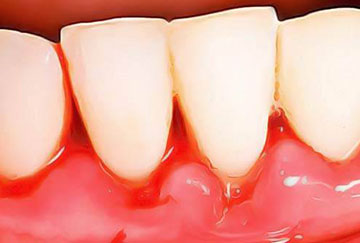

Maladies gingivales

Parodontie